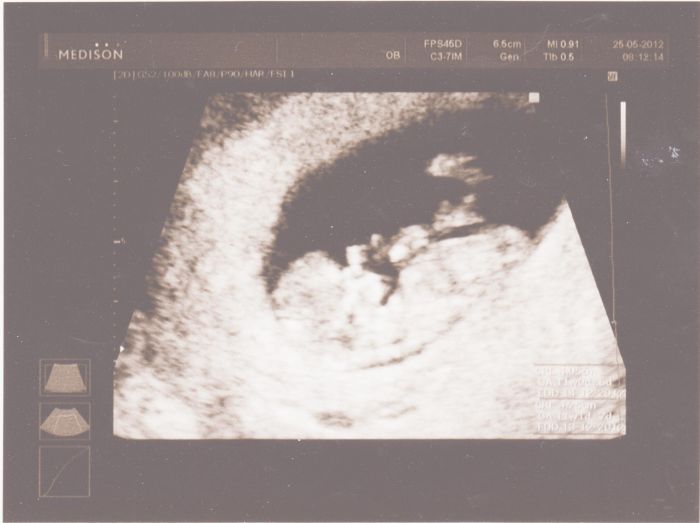

Ahoj holky tak jsem toho našeho mrňouska vyfotila mobilem snad to bude vidět. Je to 3D fotečka

Jinak je fotka ze včerejška, 12+4tt.